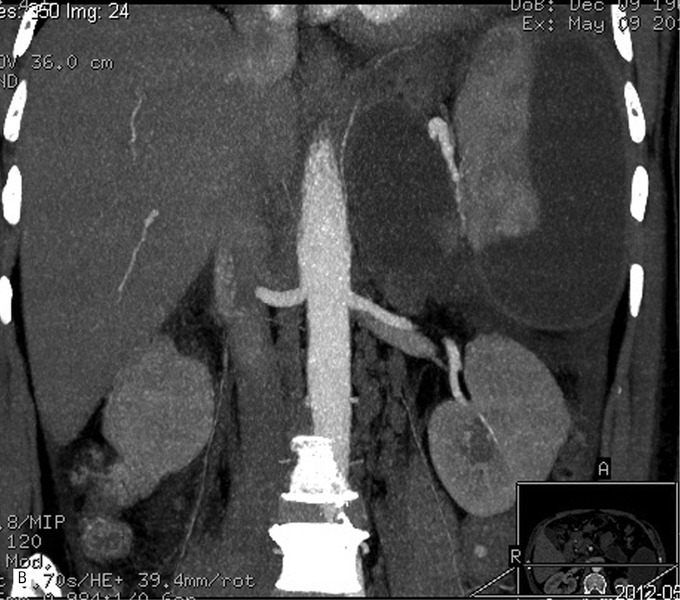

Wykonano badanie TK, które potwierdziło obecność zbiorników płynu w rzucie trzustki oraz w sąsiedztwie śledziony. Stwierdzono śladową ilość płynu w jamie otrzewnej i w lewej jamie opłucnowej (ryc. 3).

Rycina 3. Badanie TK w fazie nawrotu OZT. A. Przekrój poprzeczny przez nadbrzusze. Widoczny hipodensyjny zbiornik płynu w rzucie trzustki. Kolejne zbiorniki widoczne w otoczeniu śledziony. B. Przekrój czołowy przez nadbrzusze. Widoczny hipodensyjny zbiornik płynu w rzucie trzustki. Kolejny widoczny jest w otoczeniu śledziony.